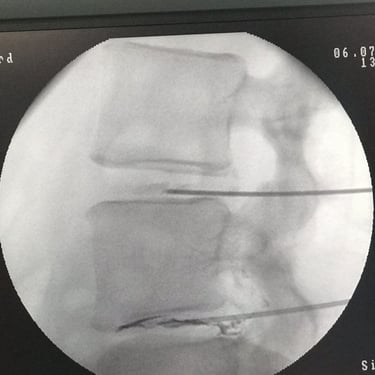

This young lady had a disc herniation at T12-L1 and was seeking treatment due to localized and radiating pain. In the images below:

The patient during the Discogel injection, the site of injection, immediate CT scans after Discogel injection, and a picture of the patient 8 years after Discogel injection. She is now a professional athlete, with her pain issues resolved